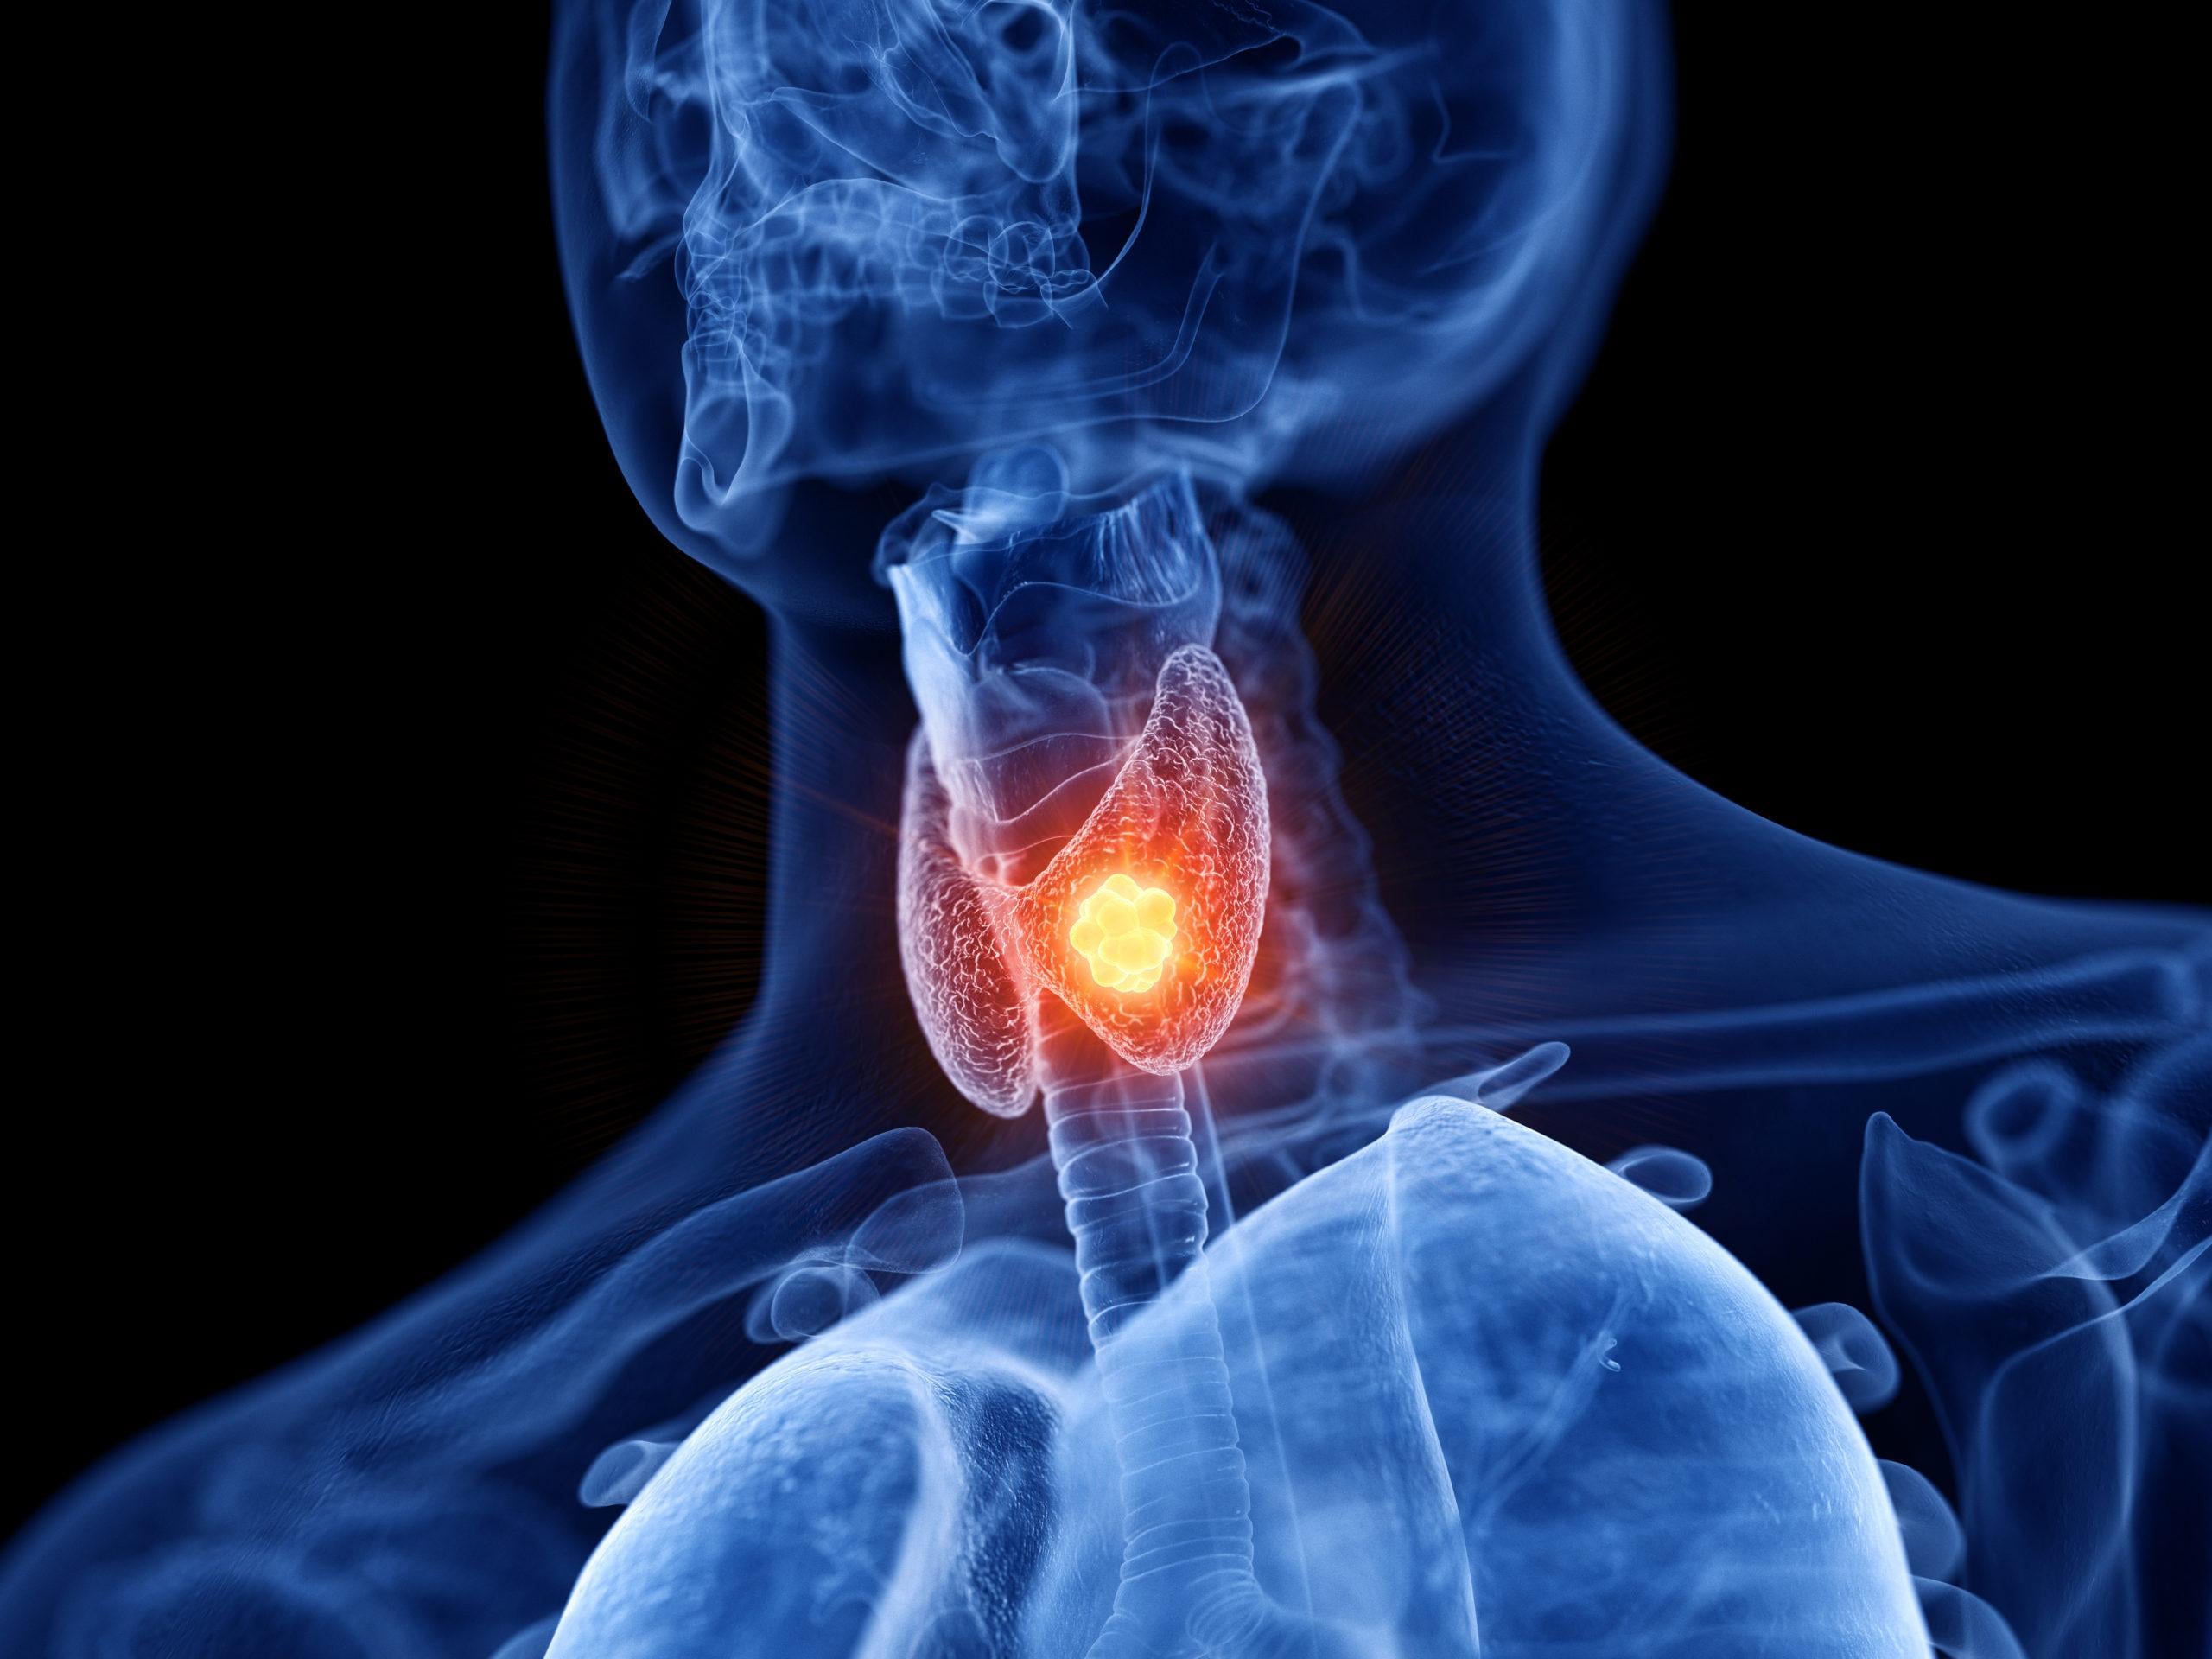

甲狀腺結節小心癌變!女音樂家治療不留痕

一名20多歲女性音樂工作者,健檢發現右側頸部有1.5厘米的甲狀腺結節,進一步超音波穿刺檢查,高度懷疑為惡性腫瘤,醫師建議手術切除。由於考量個案為年輕女性,採取經口內視鏡甲狀腺切除術,頸部不留疤,加上她的工作因素,搭配神經監測及相關手術能量器材,術後頸部外觀與聲帶完全不受影響,讓她能盡快返回工作崗位,並上台演出。

甲狀腺結節逾4厘米 惡性機率高

台北榮總一般外科主治醫師暨甲狀腺醫學中心主任陳瑞裕指出,好發於年輕女性的甲狀腺結節,是國人最常見的甲狀腺疾病,不少人都是健檢接受甲狀腺超音波檢查才發現。一般來說,結節大於4厘米以上,可能為惡性機率達10%至15%而需手術;若是結節小於4厘米,但影像表現有鈣化點、血管增生、邊緣不清楚,或壓迫氣管,也會建議手術切除。

除此之外,若在甲狀腺超音波影像及細胞學穿刺診斷下,醫師高度懷疑為非良性結節,也會建議切除。其他甲狀腺疾病,如甲狀腺機能亢進患者,對藥物產生過敏、嚴重副作用等,也可考慮進一步手術治療。

近年來,國人甲狀腺癌發生率有上升趨勢。陳瑞裕醫師提醒,大部分甲狀腺癌與個人體質有關,極少數可能與家族遺傳,或是飲食及環境有關,建議年輕女性在身體檢查時,可加做甲狀腺超聲波檢查,才能早期發現、及早治療,遠離甲狀腺癌的威脅。